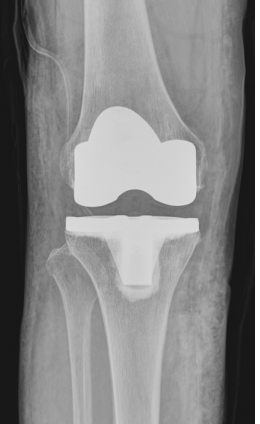

수술 전후 사례

-

수술 후